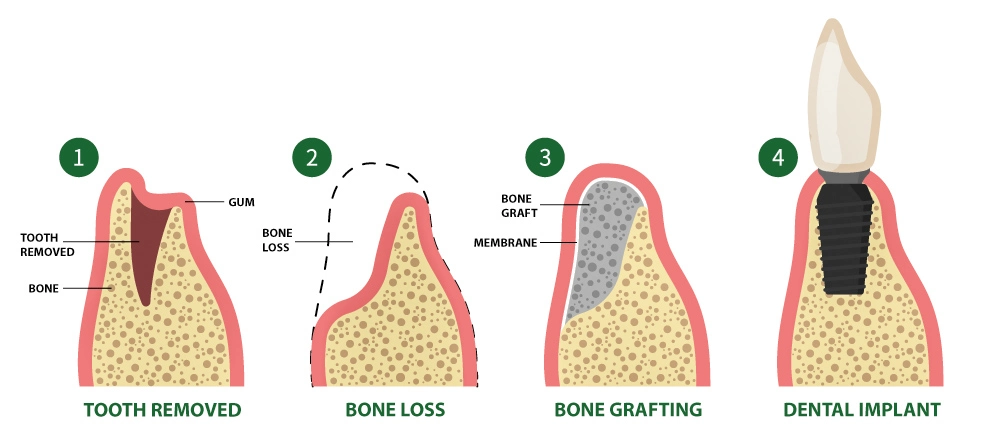

What Is Bone Grafting for Dental Implants?

Bone grafting is a precisely planned procedure that rebuilds or strengthens your jawbone so an dental implants can integrate with long-term stability.

- Implants need solid bone to anchor securely.

- When bone is thin or missing, predictability drops.

- Bone grafting restores that foundation first — before placement.

Think of it as engineering the support system behind your future smile — so the implant feels and functions like a natural tooth, not a compromise.

Why Do Some Implant Cases Require Bone Grafting?

Bone loss doesn’t announce itself — it progresses quietly.

Common causes include:

- Tooth loss months or years ago

- Gum (periodontal) disease

- Old infections or failed dental work

- Natural bone resorption over time

- Accidents or trauma

Without reinforcement, implants placed in these conditions can lose stability or fail early.

Bone grafting removes that uncertainty and turns doubt into design.